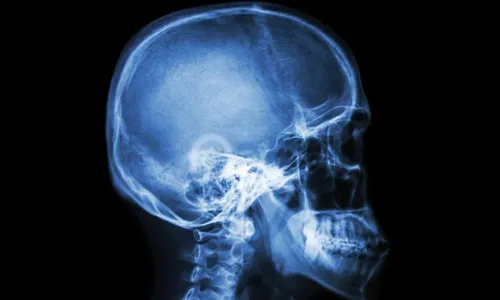

Autor Os médicos só perceberam o erro quando não conseguiram encontrar o coágulo na cabeça do paciente - imagem metropoles - Foto: Reprodução

Quatro médicos do Hospital Nacional de Nairobi, no Quênia, foram suspenso após terem feito uma cirurgia no paciente errado. Segundo informações da imprensa local, um homem, que esperava por remédios para diminuir o inchaço, foi levado para o centro cirúrgico, onde abriram sua cabeça em busca de um coágulo.

Os médicos só perceberam o erro quando não conseguiram encontrar o coágulo na cabeça do paciente. A pessoa que realmente deveria fazer a cirurgia estava esperando pacientemente em outra ala do hospital.